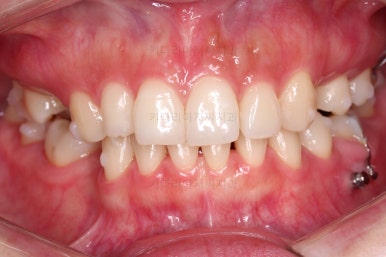

임플란트 보철까지 잘 세팅이 된 후 마무리 하게 되었습니다.

임플란트까지 잘 들어간 후 마무리 했고요.

결손공간 없이 상하좌우 모두 같은 갯수의 치아로 치료가 잘 종료되었습니다.

부산인비절라인 전후 비교해 볼게요.

얼굴에 대한 중앙선도 잘 마무리 되었습니다.

어쨌든 모든 부분에서 인비절라인으로 잘 마무리가 된 환자분이었습니다.

이상 결손치아가 5개 있었고, 비대칭, 유치잔존 환자분을 부산인비절라인으로 교정치료 후 임플란트 2개로 마무리를 한 치료사례였습니다.